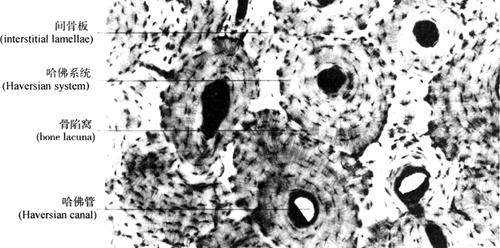

(2)密质骨(compact bone):密质骨内的骨板排列很有规律,可分为环骨板、骨单位和间骨板(图2-36)。①环骨板(circumferential lamella)分布于长骨干的内外表面,称内环骨板和外环骨板。外环骨板较厚,由数层或数十层骨板环绕骨干平行排列;内环骨板较薄,且排列不规则,骨外膜的小血管可横穿环骨板,称穿通管(perforating canal),可与骨单位中央管相连通。②骨单位(osteon)又称哈佛系统(Haversian system),位于内外环骨板之间,构成长骨干密质骨的主要部分,呈圆筒状,由4~20层同心圆排列的骨板围成,各层骨板之间有骨细胞,各骨细胞突起经骨小管穿越骨板相互连接并与骨单位中轴的中央管(central canal)又称哈佛管(Haversian canal)相通,中央管内含血管、神经、少量结缔组织。各骨单位表面有一层骨盐多而胶原纤维少的骨基质,称黏合线(cement line)。骨单位周边的骨小管都在黏合线以内返折,不与相邻骨单位表面骨小管相通。③间骨板(interstitial lamellae)是位于骨单位之间的一些被破坏后的骨单位及环骨板残余部分,无中央管,故骨细胞已退化,仅见骨陷窝和骨小管(图2-37)。

图2-37 骨磨片(400×)